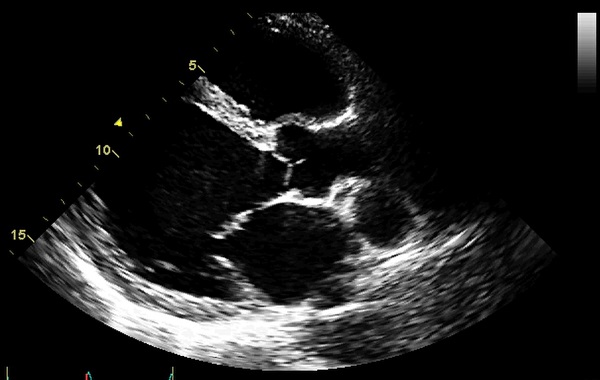

Trong đó, siêu âm tim là phương pháp hiệu quả nhất để chẩn đoán và theo dõi tiến triển của bệnh cơ tim phì đại. Siêu âm tim cũng giúp chẩn đoán phân biệt các nguyên nhân khác như hẹp van động mạch chủ, hẹp trên van động mạch chủ…

Siêu âm tim trong chẩn đoán bệnh cơ tim phì đại